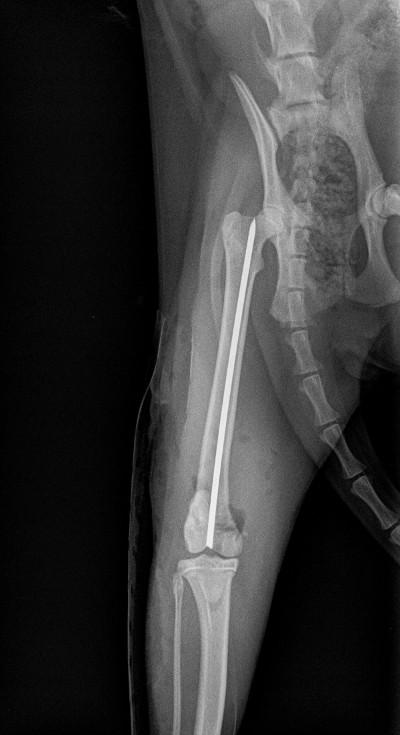

Figure 2